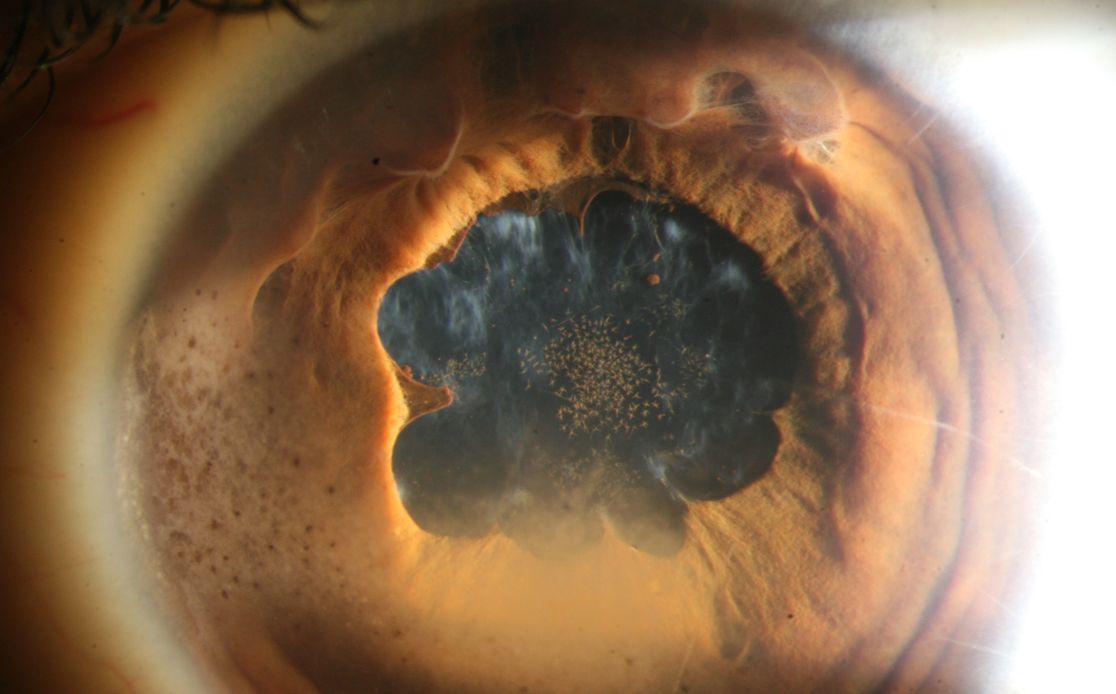

Untersuchung des Auges

Glaukom-Matinee

Die Glaukom-Matinee bietet Ihnen einen Vormittag lang aktuelle Informationen rund um das Glaukom und wird insbesondere auch kontroverseThemen aufgreifen um diese mit Ihnen zu diskutieren.